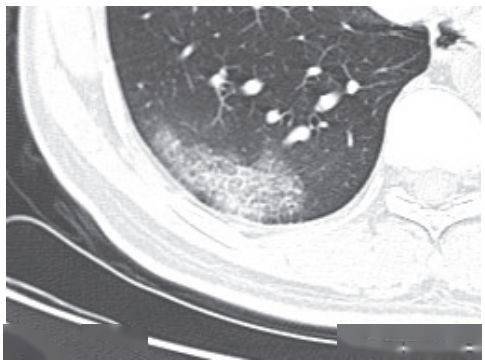

绝大多数案例出现磨玻璃病灶,最低测得 CT 值约为 - 600Hu(图 2-3),病灶内血管穿行可清晰显示;部分案例磨玻璃病灶与实性病灶共存

根据既往严重急性呼吸综合征(SARS)病理学机制,提示此为肺泡间隔毛细血管扩张充血、肺泡腔内液体渗出和小叶间隔间质水肿

图 2-3早期绝大多数病灶表现为磨玻璃密度( 共4张 )